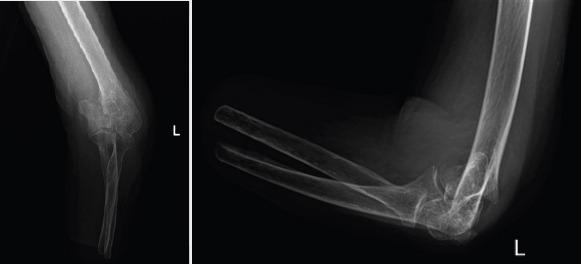

Total elbow arthroplasty is a common procedure in older patients after comminuted distal humerus fractures. However, in patients with a forearm amputation, this treatment indication is less obvious.

CASE REPORT

We report the case of an older spastic patient with bilateral forearm amputation for whom we performed a total elbow arthroplasty for a complex left distal humerus fracture. At 1 year follow-up, our patient was satisfied with the outcome as she had recovered her previous range motion and autonomy. There was no sign of implant loosening or migration on radiographs.